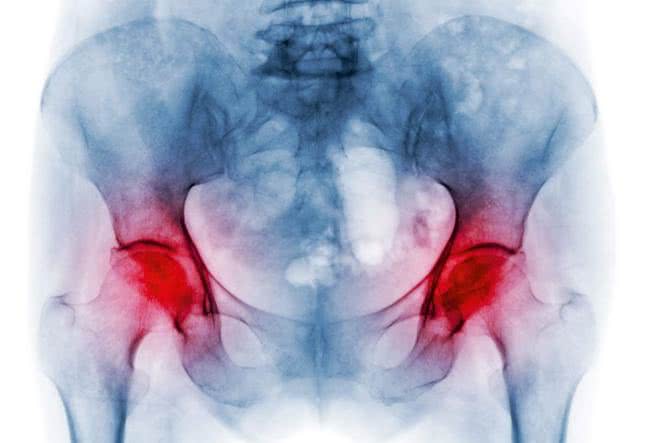

Osteoporoza to choroba charakteryzująca się postępującym ubytkiem masy kostnej, osłabieniem struktury przestrzennej kości oraz zwiększoną podatnością na złamania. Jaką rolę w przypadku osteoporozy odgrywa profilaktyka? Jak diagnozować i leczyć chorobę? Jak naturalnie wzmacniać kości?